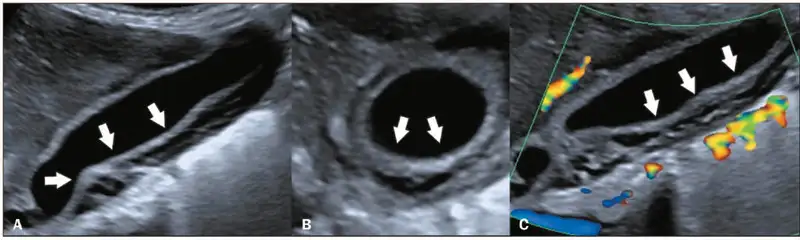

重症登革热的识别至关重要。世界卫生组织定义的预警信号包括:严重腹痛、持续呕吐、体液蓄积(腹水、胸腔积液)、黏膜出血、嗜睡或烦躁不安、肝脏肿大、红细胞压积升高伴血小板下降。任何出现这些预警信号的患者都应立即住院治疗。影像学检查在重症登革热的诊断和监测中发挥着重要作用。超声检查可以快速发现胆囊壁增厚、腹水、胸腔积液等典型的登革热表现,这些发现对于判断疾病严重程度和指导治疗具有重要价值。